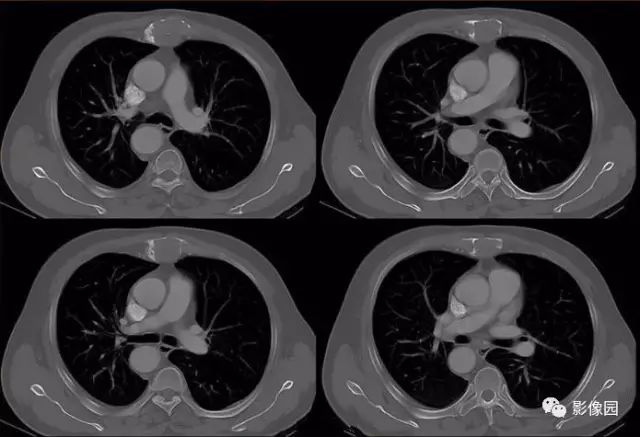

肚肚丫头: 胸骨体局部呈膨胀性骨质吸收破坏,内呈软组织密度影,可见点状钙化,增强扫描呈轻度强化,周围软组织略肿胀。考虑:1.骨巨细胞瘤;2.浆细胞瘤;3.嗜酸性肉芽肿

CT表现:特征性穿凿状、鼠咬状及蜂窝状骨破坏,边缘清楚,骨质疏松,病理性骨折及软组织肿块等表现,骨质硬化及骨膜反应少见。

骨破坏区完全为软组织取代,骨质膨胀,边界清楚,常突破骨皮质形成软组织肿块。增强扫描可见病灶轻中度强化,一般于静脉期达峰值。